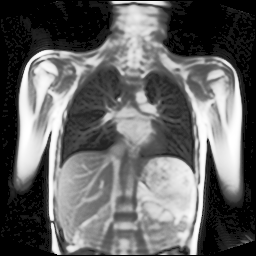

Refer to captionRefer to captionRefer to captionRefer to captionRefer to captionRefer to captionRefer to captionRefer to captionRefer to captionRefer to captionRefer to captionRefer to captionRefer to captionRefer to caption

Figure 5: Maximum inspiration (top row) and maximum expiration (bottom row) for different slice positions of one patient from back to front.

For a complete chest volume coverage, the lung is scanned at different slice positions as shown in Figure 5. At each slice position, a dynamic 2D+t image series with 140 images is acquired. For the further analysis of the image data, all images of one slice position need to be spatially aligned. We choose the image which is closest to the mean respiratory cycle as fixed image of the series. The other images of the series are then registered to this image. Our data set consists of 48 lung acquisitions of 42 different patients. Each lung scan contains between 7 and 14 slices. We used the data of 34 patients for the training set, 4 for the evaluation set, and 4 for the test set.